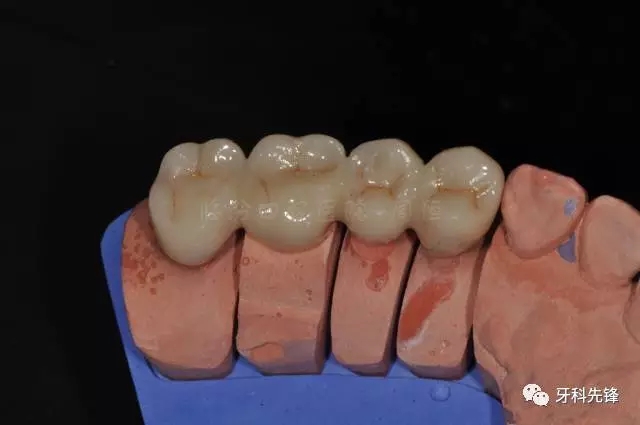

圖13牙體預備模型照

640.webp (17).jpg